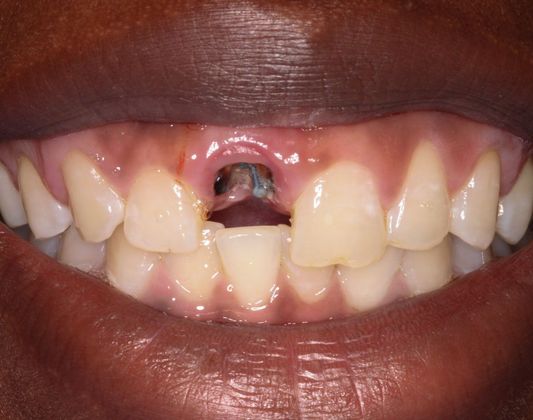

Dental Implants: Case 4

This beautiful girl presented to our Aiken office wanting to fix her front tooth. An immediate implant was placed and an immediate restoration was placed in its area. The smile was completed using an Emax implant crown much to the patient's satisfaction.